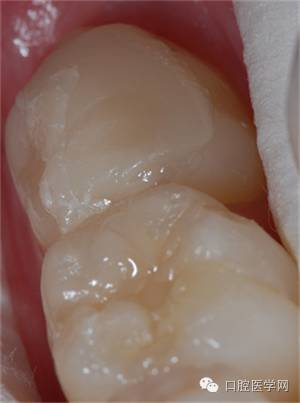

初始片

1、 评估牙体情况,患牙牙合面形态完整,可直接制作印章,若形成了破坏,可适当做一些形态补偿。

2、牙体颜色较为正常,简单比色后选用3M  Z350 body A3.5色,直接充填。